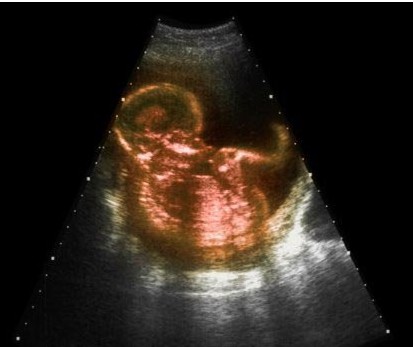

一般在用早孕棒测出怀孕之后,或者是用排卵试纸检测到呈阳性时就可以马上去医院做B超了,B超是诊断出怀孕的最正确可靠的方法。最早是在怀孕5周就能检测出来,就是在月经过期一周,在B型超声波上就会显示出子宫里面有圆形的光环,这也叫做妊娠环,环内的暗区就是羊水,其中还能够看见有节律的胎心搏动。

最早的一次B超检查是在怀孕早期,在停经6周之后。除了做一些妇科常规检查之外,还需要通过B超检查来确定宫内妊娠的正常。像宫腔内探查不到任何妊娠现象,而在子宫腔外探到异常的包块,结合一些其他的临床表现和实验室检查结果就可以考虑是不是宫外孕的可能。所以在怀孕早期通过B超能够明确是否是正常的妊娠,以及双胎或者葡萄胎。

16周左右的时候需要做一次B超的,这时候需要了解胎儿的生长发育情况的大概。然后在28周的时候进行B超复查,这时候能够清晰的了解到胎儿组织器官的发育情况,就能够了解是否有畸形,如果有畸形,就要根据医生的建议做相关对策。

最后一次是在36周到预产期之前,这个时候做B超可以明确羊水的多少,胎盘的功能,以及胎儿有没脐带绕颈等。同时B超也可以估量出胎儿的体重,明确胎儿的胎位,这样就能预测孕妇是否能够自然分娩。